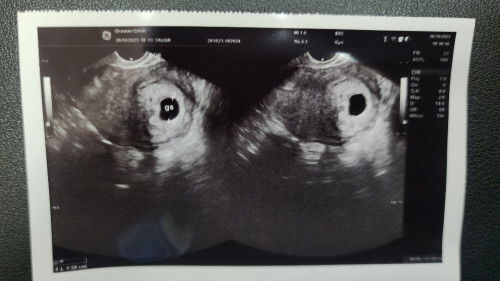

ซาวพบถุงตั้งครรภ์

หากนับจากวันเป็นประจำเดือนวันแรก เท่ากันตอนนี้ตั้งครรภ์แล้ว 9 สัปดาห์ ไปซาวด์ พบแต่ถุงตั้งครรภ์ ไม่พบตัวอ่อน หมอบอกอาจจะไข่ฝ่อหรือท้องลม นัดอีกที 3 สัปดาห์ข้างหน้า หากถุงตั้งครรภ์ใหญ่ขึ้นแต่ยังไม่มีตัวอ่อนเหมือนเดิม ให้แม่ยุติการตั้งครรภ์ แม่เป็นกังวลมากๆค่ะ #ขอคำแนะนำหน่อยค่ะ